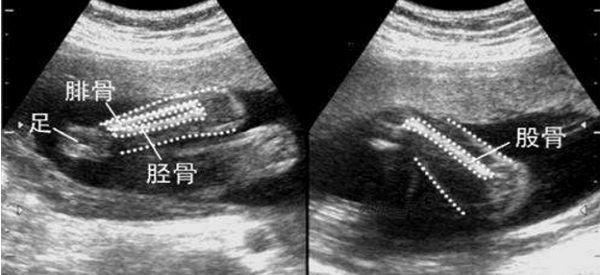

孕期胎儿股骨检查单

双顶径又称BPD,是胎儿头部左右两侧之间最宽部位的长度,而股骨长是人体中典型的长管状骨,通过这两项数据的结果并不能测出胎儿的性别,一般双顶径是医生通过这项检查的结果来观察孩子发育情况的,以此来排除胎儿是否有头盆不称,能否顺利分娩的重要依据,而股骨长是医生利用B超(或彩超)给孕妇作孕期检查时来排除胎儿发育畸形的。